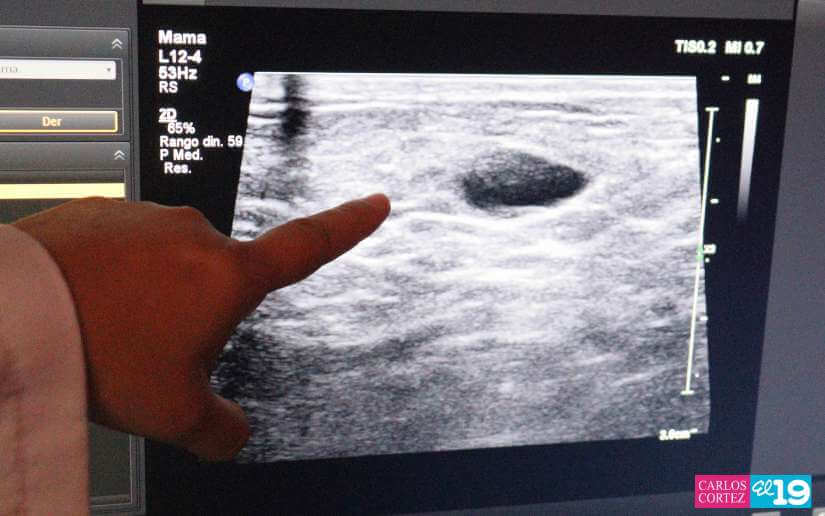

Durante la jornada se realizarán estudios de ultrasonido de útero, ultrasonido pélvico, ultrasonido de mamas, mamografías, ultrasonidos abdominales, ultrasonidos renales atención ginecológica, papanicolao, evaluación a las embarazadas, medicina natural, oftalmología, dermatología y valoraciones nutricionales.

"Estamos realizando esta mega feria de atención a las mujeres nicaragüenses en el marco de la campaña de protección de la salud de las mujeres contra el cáncer de mama. El objetivo es evaluar a todas las mujeres, hacerles una evaluación integral realizando ultrasonido de mamas, mamografías, en el caso de requerir biopsia se le van a realizar las tomas porque aquí tenemos patólogos para evaluar a cada mujer y esperamos en esta mega feria atender a unas 2500 mujeres y realizar unas 10,000 atenciones entre todos los servicios", explicó la doctora Carmen Marina Cruz Blandón.